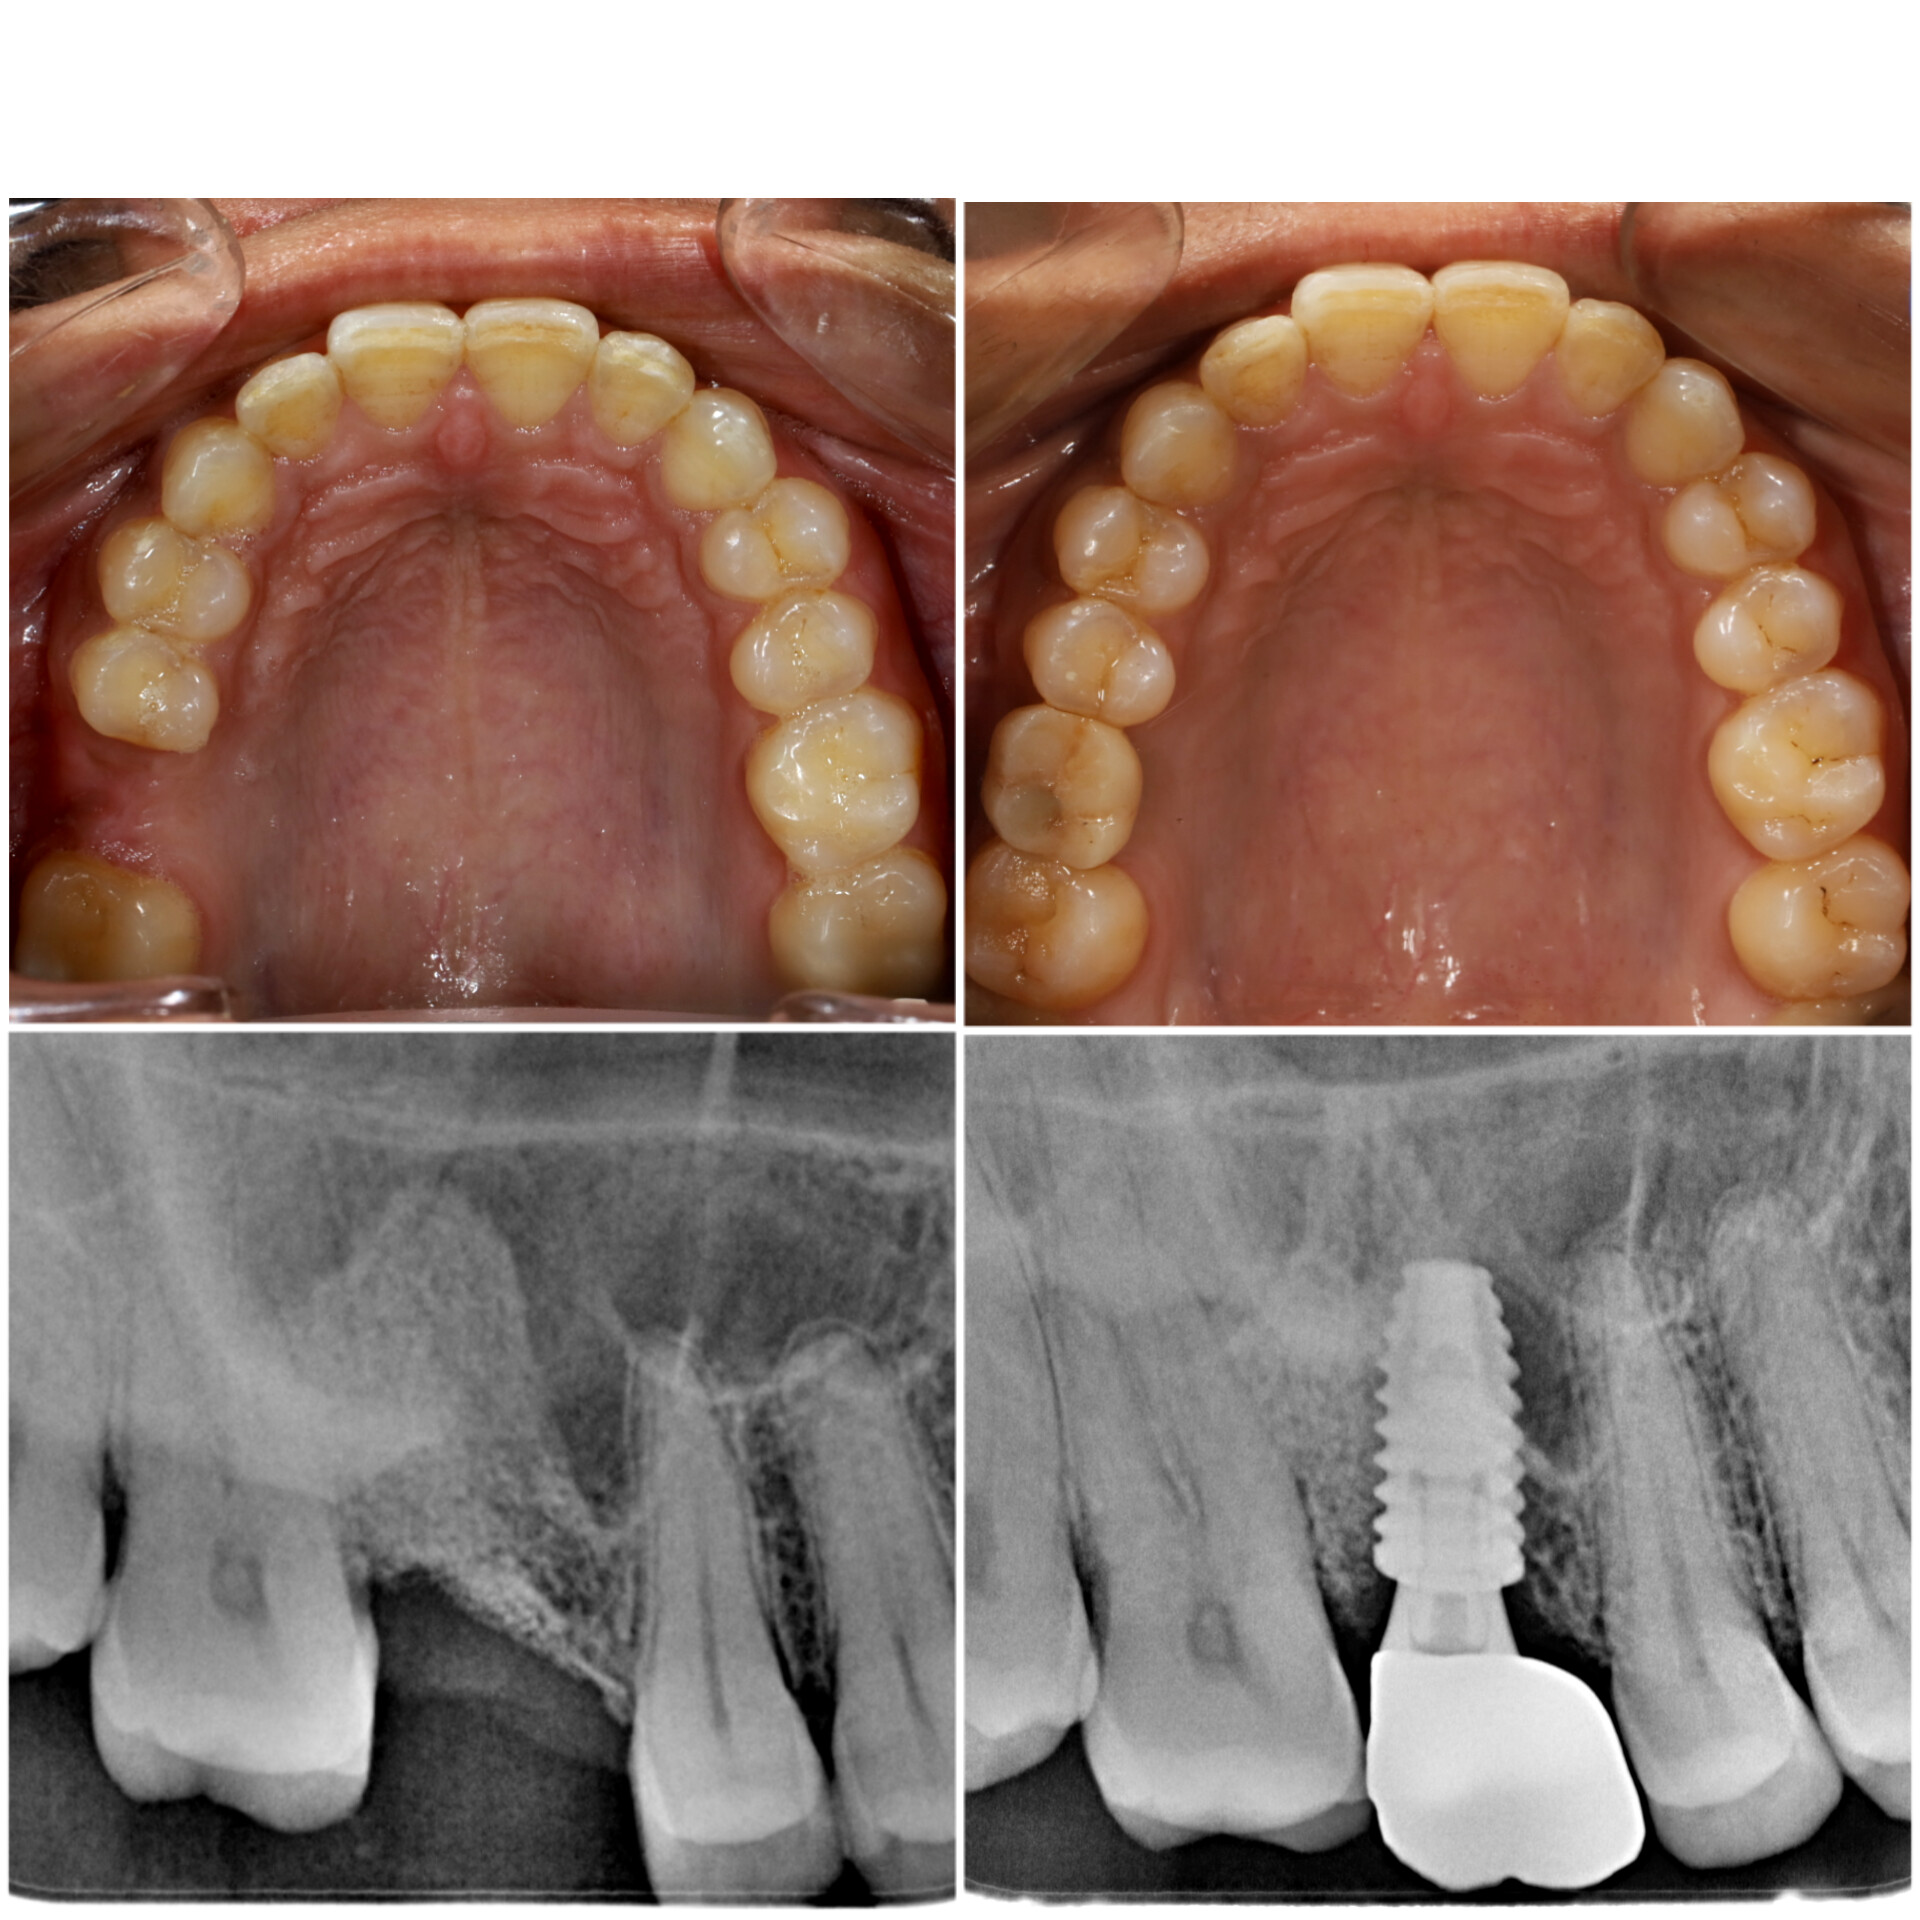

4. Dental implant success rate >97.6 %

Nobel Biocare is one of the oldest brands used in Dental worldwide. It is Swiss in origin and currently, a No.1 in the dental implant industry. It is produced from commercially pure titanium. It is employed for Single implant surgeries, multiple implant surgeries such as implant supported plates, bridges, and specialized systems. For example All-on-4, This brand has unmatched durability, excellent bone integration, and formation, as well as highly superior implant stability. It has a Xeal abutment surface for enhanced mucointegration and TiUnite surface and TiUltra surface which enhances Osseointegration, even when the conditions are challenging. As Nobel Biocare is a Dental Implant brand used worldwide, we opt for it, so that the postoperative follow-ups for patients visiting us from abroad becomes easier for them, as they can consult dentists who employ Nobel Biocare. We provide our patients with the best prosthetic crowns, bridges, abutments, manufactured at NobelProcera, which remains a leader in manufacturing dental prosthesis.